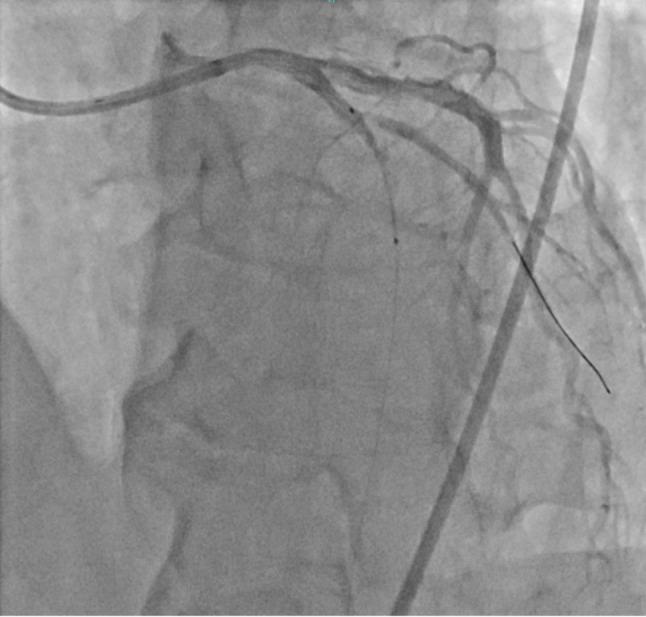

A 65-year-old male were re-administered to our hospital due to recurrent VSP. He was during follow up after undergone emergency VSP closure surgery 2 months earlier, utilizing the bovine double patch technique via left ventriculostomy. The initial VSP was located in the apical part of the interventricular septum, while the recurrent VSP appeared in the upper middle portion of the interventricular septum (Fig. 1). As the previous patch remained intact, the second surgery employed the bovine double patch technique via right ventriculostomy. The patient's condition remained stable without the development of heart failure symptoms.

一名 65 岁男性,因 VSP 反复发作再次入我院。他在 2 个月前因 VSP 行紧急 VSP 关闭手术,通过左心室造口术使用牛双补片技术。初次 VSP 位于室间隔心尖部,而再次 VSP 则出现在室间隔中上段(图 1)。由于先前的补片保持完整,第二次手术通过右心室造口术使用牛双补片技术。患者情况稳定,未出现心力衰竭症状。